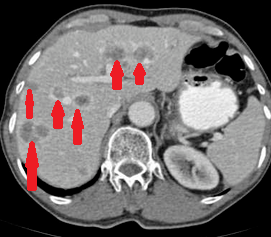

Εικόνες CT κοιλίας, που δείχνουν κυστικού τύπου βλάβη, μεταξύ ήπατος και ηπατικής καμπής του κόλου, σε επαφή με το εξωτερικό στρώμα του εντέρου, με πεπαχυσμένο τοίχωμα και χαμηλής πυκνότητας κέντρο (Ευγενική παραχώρηση Dr. V. Penopoulos)